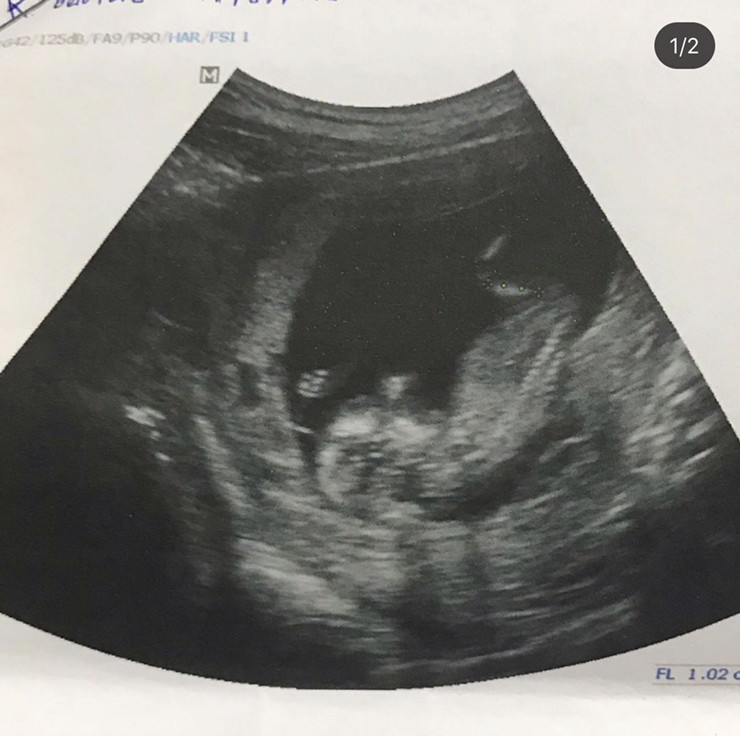

รูปที่ซาวด์ตอน10w5d ค่ะ

ตอนนี้ 13 week จ้า